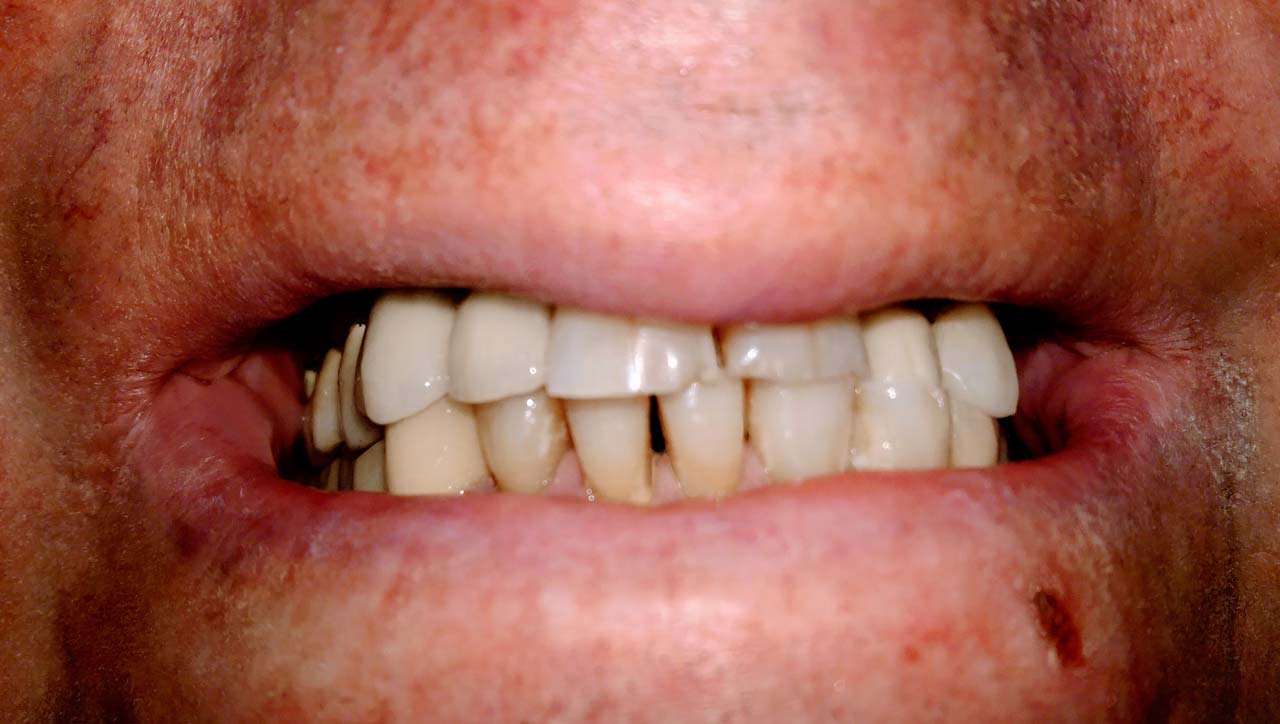

Harapás helyreállítása asztétikus cirkónium koronákkal

Rágófunkció esztétikus helyreállítása azonnalterhelhető svájci IHDE implantátumokkal és porcelán koronákkal.

A régóta fennálló foghiány és a mozgó fogak miatt a páciens nem tudott jól rágni és harapni, illetve mosolyogni sem mert már jó ideje. A leggyorsabb és a legesztétikusabb megoldás az ilyen esetekre az IHDE azonnal terhelhető implantátumok behelyezése, és az azokra rögtön elkészített porcelán koronák elkészítése.

A teljes munka - az implantáció, a végleges koronák elkészítése - 5 munkanapot vett igénybe.